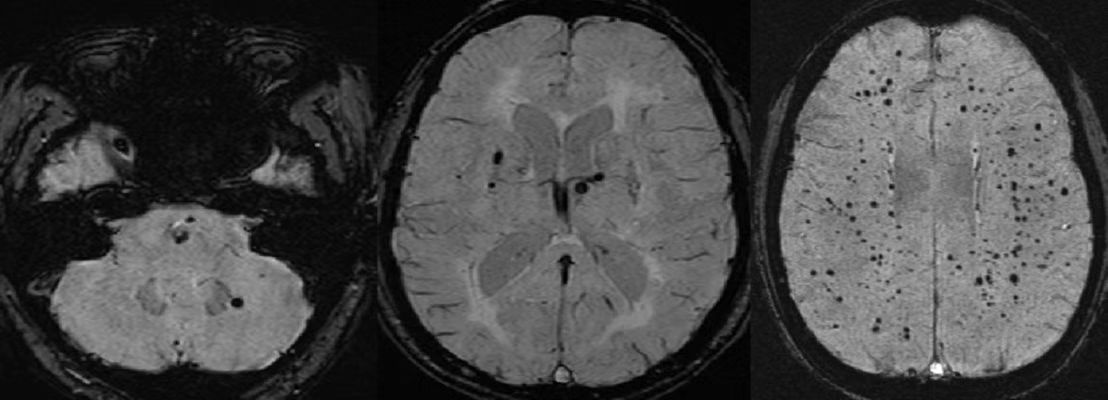

脑微出血灶主要通过MRI(T2 * -GRE和SWI,偶尔DWI)技术检查来明确诊断,而通常比较常用的颅脑CT对其无能为力,因此选择检查方法很重要。那么我们来看看脑微出血在MRI上的影像学表现。

上面三幅图像就是MRI(SWI序列)成像,图片中的多发黑点(专业术语:低信号)就是脑微出血灶。